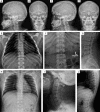

Figure 1

Phenotype of skull, thorax and spine. Lateral skull radiographs show mildly thickened calvarias of S1 (A, B) and S2 (C–D). S1 and S2 show an open bite (A, C). Radiographs of chest and spine show broad (oar-shaped) ribs (S1 at 17 years (E, F) and S2 at 14 years (H)), broad vertebral bodies, platyspondyly and irregular endplates (S1 at 17 years (G), S3 at 18 years (J)). S1 shows a bell-shaped thorax (E). Radiographs of lateral spine additionally illustrate anterior beaking and irregular vertebral end plates (J). Lateral spine radiograph of the lumbar area shows platyspondyly with scalloping of the posterior end plates (S1 at 12 years (G)). Anterior inferior beaking of the cervical spine of S3 at 20 years (I). S1–S4, subjects 1–4.